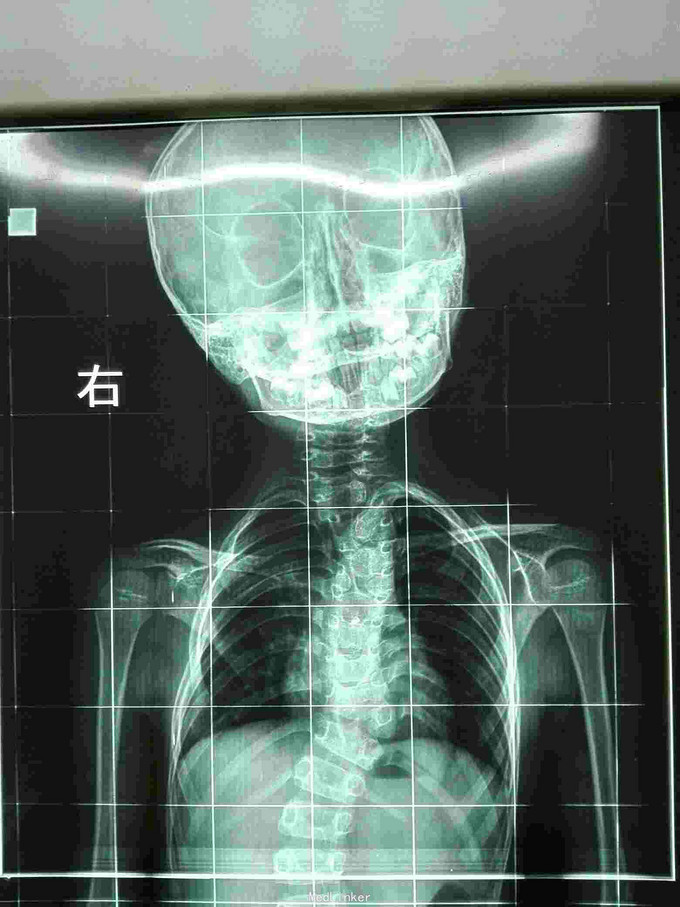

先天脊柱畸形

先天脊柱畸形8年。

严重脊柱畸形病例

先天性脊柱侧凸畸形

脊柱先天畸形